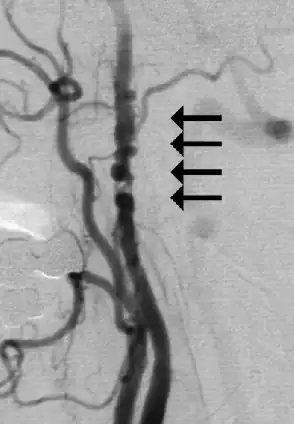

| Angiogram showing narrowing of the arteries in the neck in a women with a TIA[1] | |